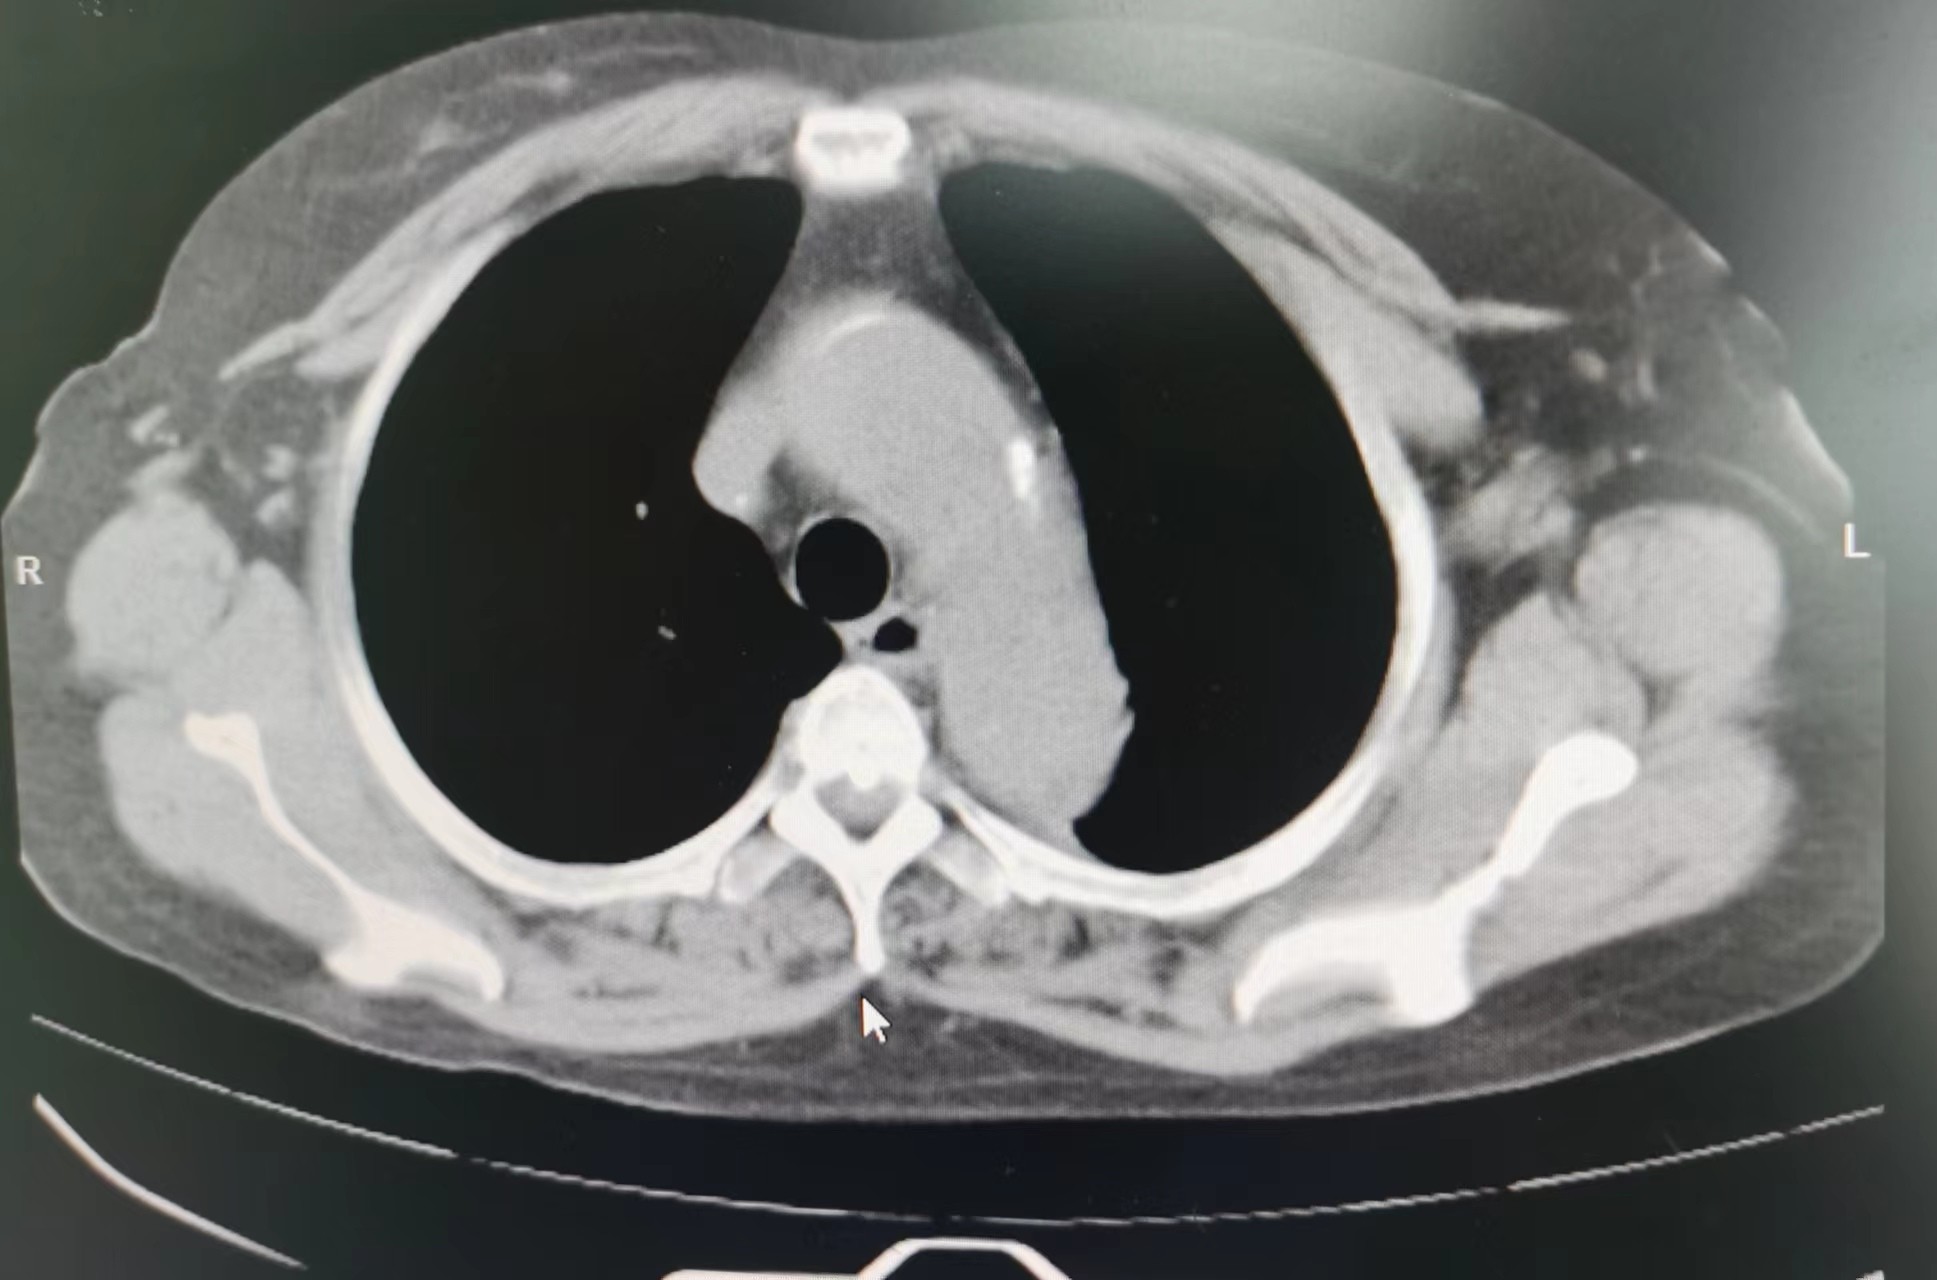

2023年11月,廖阿姨开始出现上腹部不适及胸痛,在外地医院住院治疗,当时查胸部CT考虑为:1.肺纤维化;2.双肺小结节;并经完善其他相关检查后考虑腹痛为:慢性胃炎(未行胃镜检查)。因临近过年,廖阿姨决定回本地过春节,在外地住院治疗10余日后和我院血液净化中心联系透析事宜。2023年12月,廖阿姨在我院透析时仍诉有上腹痛,值班医生经过仔细查体,感觉廖阿姨不像单纯慢性胃炎那么简单。首先,廖阿姨剑突下压痛不明显;其次,廖阿姨腹痛呈阵发性加重,加重时疼痛可累及左侧胸部,严重时胸部疼痛呈撕裂感,这些不像仅有慢性胃炎的症状。我院肾内科主任、主任医师李友河会诊后建议患者住院进一步检查,廖阿姨当日办理了住院。廖阿姨住院期间,肾内科予以相关治疗后其腹痛逐渐缓解,但未完全消失,经李友河主任、主管医生反复沟通和讲解病情后,廖阿姨及其家属终于认识到病情发展的严重性,从原本不愿检查的态度转变为同意完善胸部CT检查。经胸部CT平扫,结果为:1.主动脉夹层可能,建议进一步增强检查;2.右肺、左肺上叶少量慢性炎症;3.主动脉、冠状动脉硬化;4.心包少量积液,左侧胸腔少量积液。

当结果出来后,李友河主任第一时间查看了结果,并马上和患者家属沟通,建议廖阿姨马上行胸部CT增强扫描,同时,我院将立即开通绿色通道,转入我院深度帮扶医院——广东省人民医院进行救治。当晚,廖阿姨胸部CT增强结果提示为主动脉夹层,我院立即派出救护车和医护人员,全程护送廖阿姨至广东省人民医院进一步救治。廖阿姨先后在省人民医院心脏急危重症监护室、心内五科治疗,3日后,省人民医院专家为其行胸主动脉覆膜支架腔内隔绝术+暂时性经静脉起搏器系统的置入等治疗,2024年1月廖阿姨好转出院,并继续预约到本院透析。廖阿姨及家属在省人民医院出院后,十分感激我院及省人民医院的救命之恩,他们认为在省人民深度帮扶我院以来,佛冈县人民医院打出了“省医就在家门口的口号”,不管是佛冈县人民医院的医疗技术,还是医德医风均取得了很大的进步。随后,廖阿姨特地送来了锦旗,感谢全体肾内科医护人员的救命之恩。我院肾内科坚持“以患者为中心”的理念,进一步改善医疗服务,满足患者日常就医需求,为患者提供全周期的诊疗服务,在不断提高诊疗水平的同时,丰富服务内涵建设,改善患者就医体验,为广大群众生命健康保驾护航。科室简介